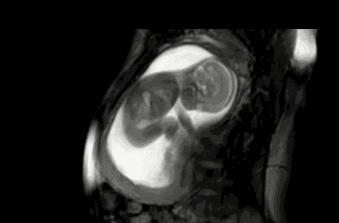

1.胎儿是臀位。

怀孕中期,胎儿越来越大,孕妇子宫内越来越狭窄,胎儿需要用尽全力才能舒展被挤压的手脚,如果孕妇感觉到右边有胎动,而且是光滑的,不规则的圆形,那么就是胎儿的背部。

2.胎儿是横位。

胎儿横位的时候,胎儿的头部和足部在孕肚的两侧,如果双脚在孕肚右侧,那么胎动时,自然在孕肚腹部右边了。

3.胎儿是头位。

胎儿准备入盆的过程里,胎儿会往下走,胎动会变得十分频繁,胎儿的双脚会不停地踢向孕妇的腹部,孕妈偶尔还会看到宝宝隐约的小脚丫呢。

如果胎儿的胎位是枕左前或者是枕右前,这是正常的胎位,有利于顺产,胎动多数出现在右侧。

怀孕7个月,胎位还没有固定,羊水量多,胎儿很可能变换各种体位,因此胎动在右侧也是正常的,有时候胎动还会出现在左侧,或者是孕肚中央,胎儿力度大证明胎儿发育好。

5.胎儿的体位。 如果胎儿的头部在左侧,胎儿的四肢在靠近孕妇肚子右侧的地方,那么胎儿做幅度大的动作的时候,胎动会比较明显,孕妇能感觉到胎儿在拳打脚踢。